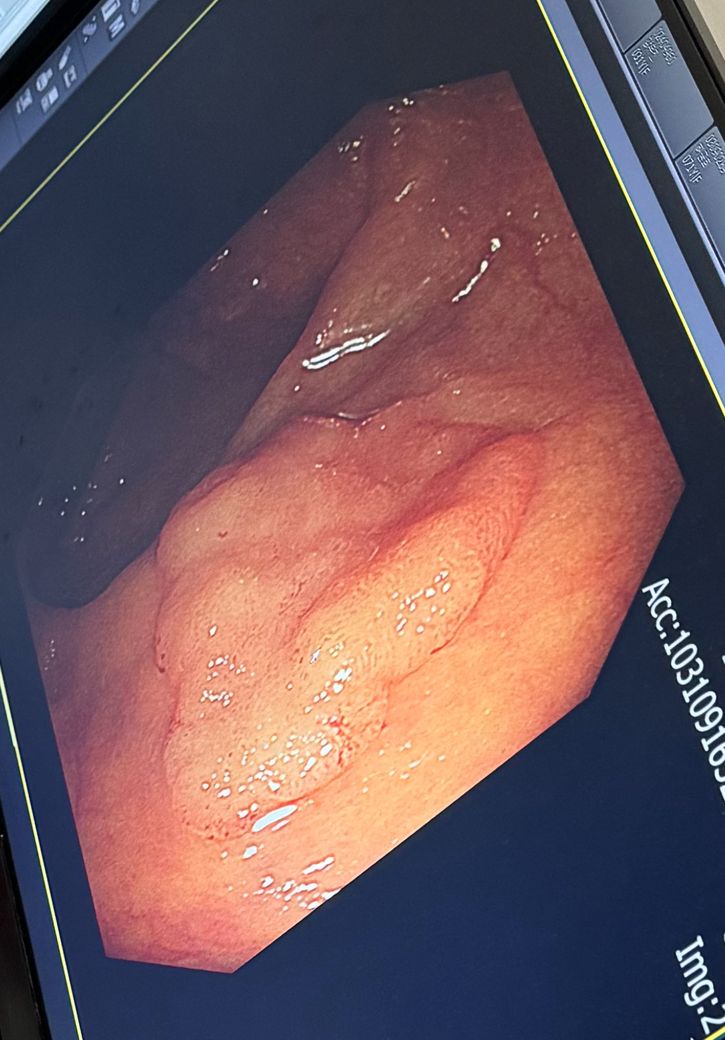

• 2번 째 사진

가장 좋은 방법은 내시경 점막 절제술이나 내시경 점막하 박리술등으로 병변전체를 제거하고 절단면까지 확인하는게 좋을거 같긴 합니다.

조직검사를 해서(?) 큰 문제없는 경우는 모르겠지만,,고도선종이나 조기위암 경우는 잘 제거하는게 좋긴할거 같습니다

• 용종을 제거한 뒤에 용종의 변연이 남았을 가능성이 있는 변연 부위로 전기소작을 해서 재발 가능성을 줄이는 치료는 가능한 치료이며, 시행되는 치료입니다.

• 용종이 높이가 얇고 부위가 넓어서 한번에 충분하게 제거하기가 어려웠을 것입니다

그렇게 하는 경우 천공의 위험이 있으니까요

하지만 천공을 걱정하여 조심조심 제거하다 보면 당연히 남는 부분이 있을 것입니다

그것을 떼도 되고 말씀라신 것처럼 전기소작으로 지져도 됩니다

많은 병원에서 하는 방법이니 걱정하지 마세요

치료는 잘 되신 것 같습니다.